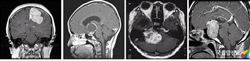

악성 뇌종양

2009.08.21

양성 뇌종양

2009.08.21